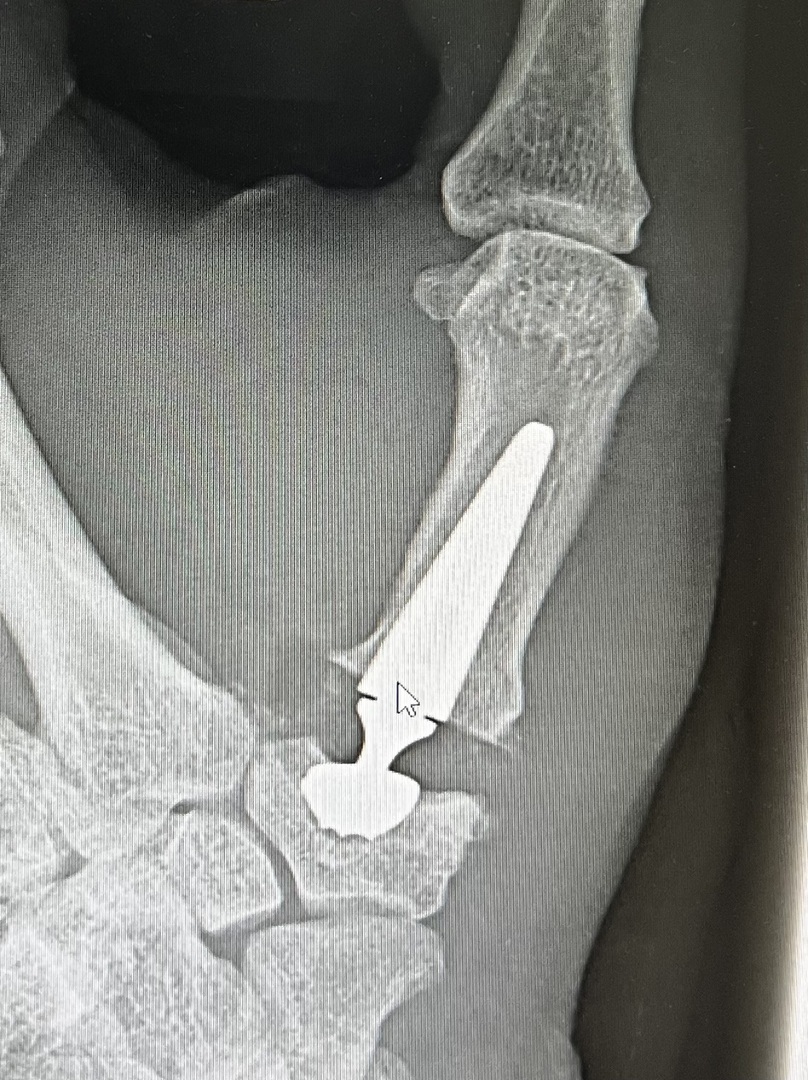

Sattelgelenkprothese Typ Touch

In unserer Praxisklinik wir bei einer Arthrose im Sattelgelenk als ein sehr erfolgreiches Verfahren eine Prothese in das Daumensattelgelen eingebaut. Wir verwenden ein sehr gutes Impantat von der Firma Medartis und zwar die Touch Prothese.